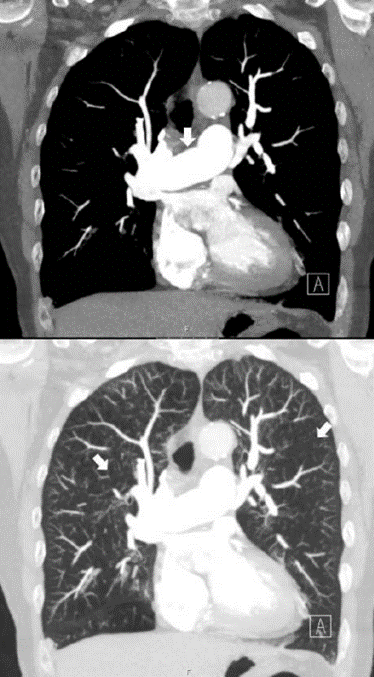

Vad ser du på bilden?

DT thorax utförd med intravenös kontrast på lungembolifrågeställning. Två koronara snitt i höjd med truncus pulmonalis; den övre bilden i mediastinumfönster och den nedre i lungfönster.

Notera hur breddökad truncus pulmonalis (indikerad med pil på den övre bilden) är i förhållande till arcus aortae, vilket är ett tydligt tecken på högt tryck i lungkretsloppet. Notera också generellt fläckvis varierande attenuering (kärlen syns inte, svart bild liksom, kan innebära luft som fastnar i experium) i lungparenkymet (indikerat med pilar i nedre bilden), ett mönster som kallas mosaik pattern. Ett litet infiltrat ses lateralt-basalt i höger lunga.

Vad säger oss fyndet av ”mosaik pattern i inspiration” och ”air-trapping” på DT?

CTEPH kan ge denna bilden med pulmonell hypertension